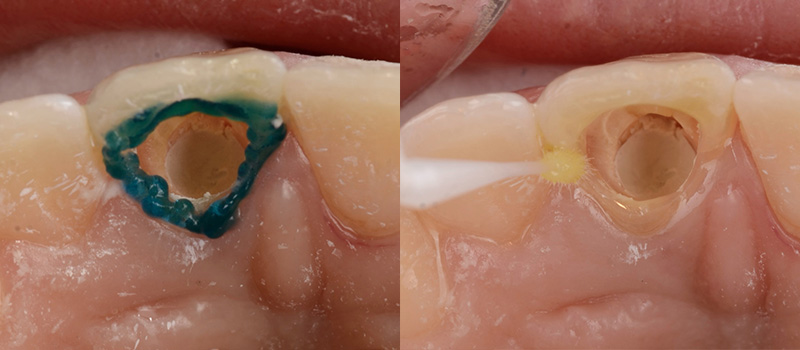

Le composite est déposé et la chambre pulpaire soigneusement nettoyée en prenant soin de ne pas affiner les parois dentaires résiduelles. Une attention particulière est portée au nettoyage des zones de cornes pulpaires en contre dépouilles risquant d’être des réservoirs à produits de dégradation.

Fig. 06 : nettoyage soigneux.

Ce mm sous-gingival est obturé avec un ciment étanche (oxyphosphate par exemple) pour protéger l’obturation canalaire. Il est important de ne pas recouvrir les parois internes dentinaires par un matériau ou par un adhésif qui empêcheraient la diffusion du produit d’éclaircissement dans l’ensemble de la zone coronaire.

Fig. 09 : bouchon canalaire.

Avant de remplir la cavité par le produit d’éclaircissement, une attention particulière est portée sur le maintien d’un bouchon palatin étanche pendant le traitement.

L’émail périphérique est mordancé 15 secondes puis un adhésif universel est frotté uniquement sur ce pourtour, en évitant de l’étaler à la soufflette pour ne pas obturer les tubuli dentinaires. Cet adhésif est photopolymérisé 20 secondes.

Fig. 10 & 11 : mordançage amélaire et adhésif universel polymérisé.